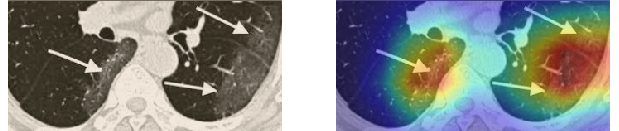

In order to make our models more transparent and provide detailed visual analysis, we present the Grad-CAM localization maps obtained by different models. We consider CT images with COVID-19 abnormalities from the test set of each dataset and highlight the important regions considered for the prediction. For the SARS-CoV-2 dataset we use the Inception V3 model. Figure 13 shows the original CT images and their localization maps. Our model is capable to detect regions that show abnormalities in the CT scans.

In a similar way, we consider classifying the test CT scans from the COVID-19 dataset by the DenseNet169 model and highlight the important regions considered for predictions. We present the original CT images and their localization maps in Figure 13. We can also see that our model is capable to detect the COVID-19 related regions as marked (small square in some images) by expert radiologists.

A wide variety of typical and atypical CT abnormalities have been reported for COVID-19 patients in various studies [58, 59]. So, we tested our models on external CT images extracted from these two publications as they feature typical findings of COVID-19 pneumonia marked by specialists. In order to make sure that not any of the extracted images are unintentionally included in our datasets, specifically the COVID19-CT dataset, we use the model trained on the SARS-CoV-2 dataset. First, the InceptionV3 model is employed to classify the extracted CT images. The model is able to correctly classify the given CT images as COVID-19. Second, in order to interpret the model’s generalization capabilities, we apply the Grad-CAM technique to visualize the regions of abnormalities that are considered. By assessing the different CT images in Figure 15, we can see that the model accurately localizes the disease-related regions. Even more interesting is the fact that the model ignores any specific marks in the images like letters and only localizes the COVID-19 related regions. These visual explanations show the success of our models to learn relevant, generic visual features related to COVID-19 and are capable to correctly classify CT images outside the datasets on which they are trained.